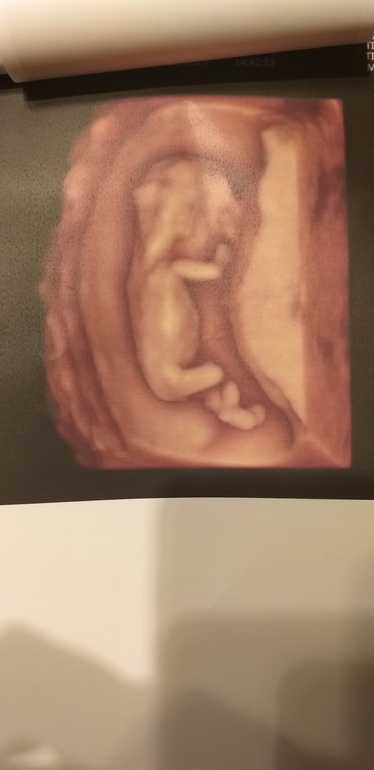

59мм, сб 155, носик есть, твп 1.3 (срок 12.4)

Посмотрели все органы, все они на месте)

Я довольна как слон! Ииии...... пол. Показали нам бугорок - сказала она, что бугорок у нас... ДЕВОЧКИН!!!!!!!!! Кто был у Пятых, не ошибалась? Просто с сыном мне сказали 80% мальчик еще в 11.5 недель. Но доктор другой был. Короче пока мы настроились на девочку, как и моя интуиция) это просто непередаваемые ощущения - представлять себя мамой разнополых детей))))) кружок пока не закрашиваю, жду второго скрининга)

Сейчас она еще подросла, уже на человечка похожа)) Тут еще всё же инопланетяшка)))